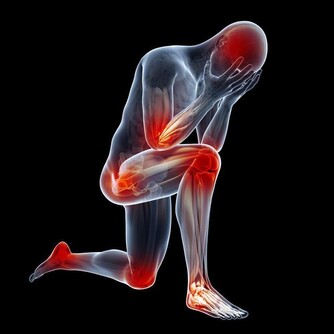

提到血栓,我們往往會感到恐懼,因為它往往跟心梗、腦梗、肺血栓等有關,而這些疾病的共同點就是可能讓人猝死。所以,對於血栓我們都要引起足夠的重視。

但另一方面大家也不用過於擔心,從出現血栓到真正引起嚴重病症,中間會經歷很長時間,因此我們如果能識別血栓早期預警信號,就可能讓你避開那些致命的後果。

1. 腿部腫脹疼痛

如果血栓源於腿部,當它形成時,靜脈中會出現腫脹,這會導緻小腿肌肉疼痛。更糟糕的是,小腿組織很厚,因此身體系統難以消除血栓。所以,如果你發現自己吃了消腫藥卻不起作用,那就說明可能存在血栓。

8. 經常腿抽筋

每個人都會時不時抽筋,但你要知道,與凝血有關的脫水也能導致肌肉痙攣。所以,如果小腿抽筋變得頻繁,這是一個嚴重的跡象,表明可能存在血栓。通常,緩解痙攣的方法是向後彎曲足部以拉伸肌肉。如果這種做法沒有幫助,並且疼痛增加,原因很可能就是血栓。

9. 腳和小腿疼痛

小腿上的深靜脈血栓,會造成嚴重的疼痛,使人步行困難並且坐著也會疼。不僅如此,腳部疼痛也是其後果之一,由於血栓妨礙血液流向足部,導致足部缺氧,造成嚴重不適。